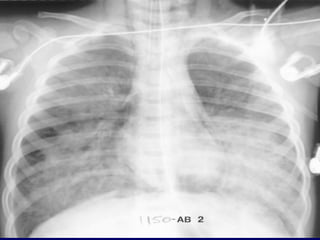

• 4.

cc At the bedside,chest radiography remains the reference for lung imaging in critically ill patients. However, radiographical images are often of limited quality • Movements of the chest wall • Film cassette posterior to the thorax • X-ray beam originating anteriorly, at a shorter distance than recommended and not tangential to the diaphragmatic cupola . Mistaken assessment of : cc • Pleural effusion • Alveolar consolidation • Alveolar-interstitial syndrome Bedside Chest Radiography in the Critically ill

• 5.

(posterioranterior) position. Note that thex-ray tube is 72 inches away. the supine AP (anteriorposterior) position the x-ray tube is 40 inches from the patient.